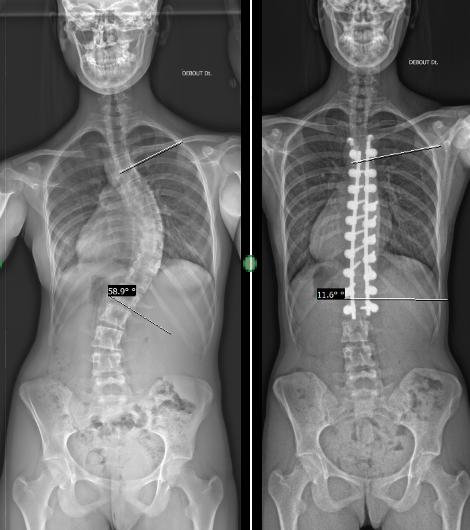

Photo libre de droit de Radiographie Du Rachis Patient Adulte Montrent Fix Chirurgie Scoliose Par Tige De Métal Longue Et Beaucoup Vis Pour Courbure Rachidienne Chez Les Personnes Adultes Concept De Médecine